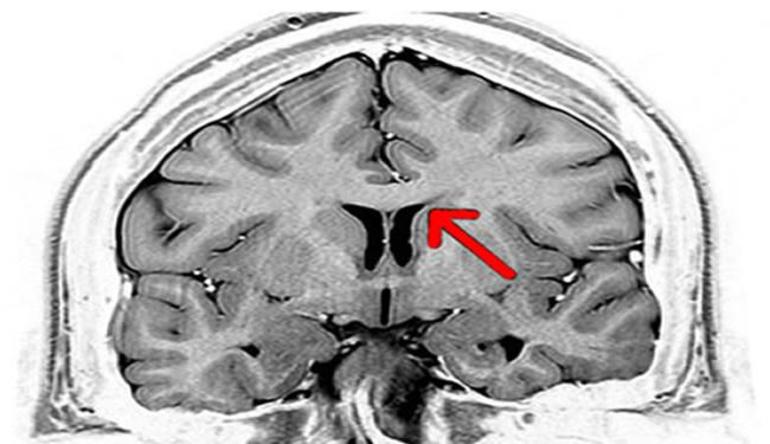

- Гипоплазия — специфический порок развития, который характеризуется чрезмерно маленькими размерами артерий. Если в других мозговых отделах кровообращение нормальное, патология будет развиваться без каких-либо симптомов. Гипоплазию можно обнаружить при проведении комплексной диагностики работоспособности головного мозга. Подобное отклонение отчетливо видно на снимках МРТ.

- Аплазия представляет собой состояние, когда ВК не замкнут из-за отсутствия соединяющей артерии. Примечательно, что такое отклонение может развиваться и в передней, и в задней части. Однако последний вариант встречается намного чаще. Если артерия есть, но развита очень слабо, диагностируется частичная разомкнутость круга. Обследование разомкнутого круга происходит при помощи магнитно-резонансной томографии. Причиной возникновения подобной патологии является остановка развития на этапе формирования плода.

- МРТ на сегодняшний день является самым точным способом обследования. Диагностика осуществляется на магнитно-резонансном томографе. Принцип работы заключается в воздействии магнитным полем на клетки тела с последующей фиксацией их реакции. Такой диагностический метод позволяет получить информацию о состоянии любого органа человека. Не является исключением и сосудистая система. В силу того, что обследование неинвазивное, процедура считается безопасной. Радиоактивное облучение при этом не используется.